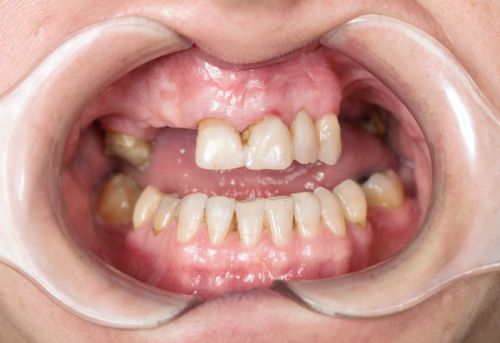

Samodzielna korona nie obciążająca zębów sąsiednich - to dzisiaj możliwe.

+ brak konieczności szlifowania zębów

+ brak zalegania resztek pokarmowych pod mostem